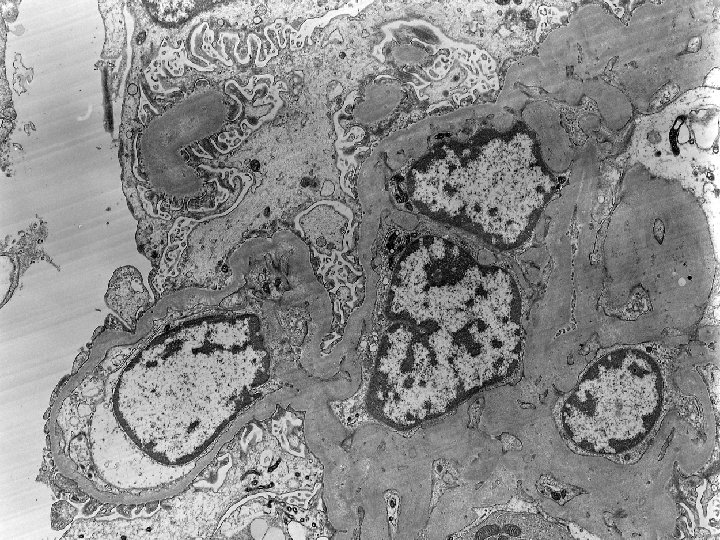

Diagnosis: Renal Biopsy(2 years post-transplantation): Moderate parenchymal scarring and tubular loss with chronic inflammation.

Diagnosis: Renal Biopsy(2 years post-transplantation): Moderate parenchymal scarring and tubular loss with chronic inflammation. Borderline changes with focal moderate tubulitis. EM is pending. Banff scores: (G 0, CG 0, I 2, CI 2, T 2, CT 2, V 0, CV 2, AH 1, MM 0)